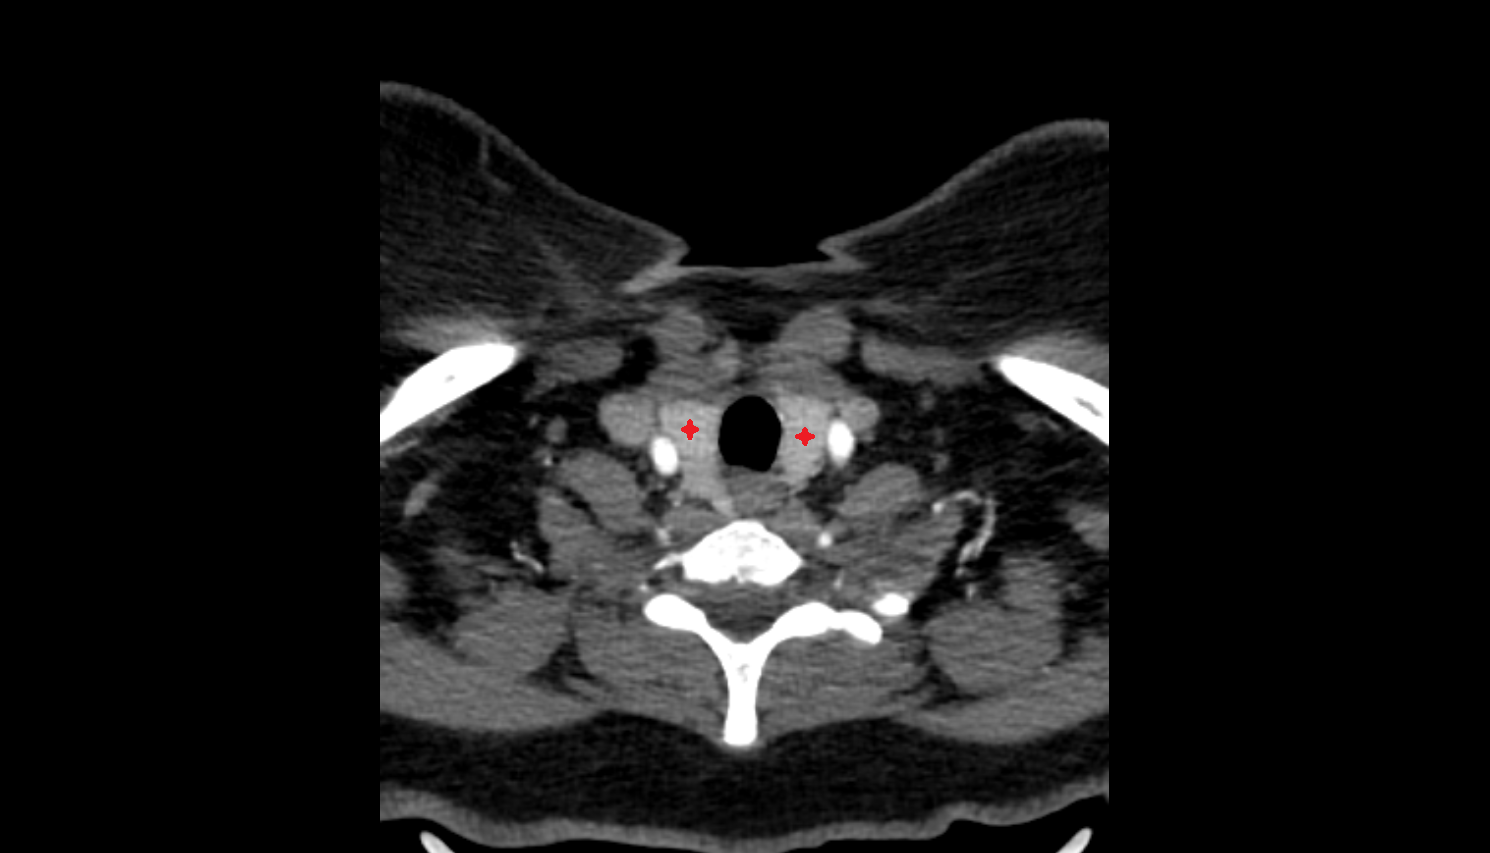

- Carotid bifurcation

- Internal carotid artery (cervical part)